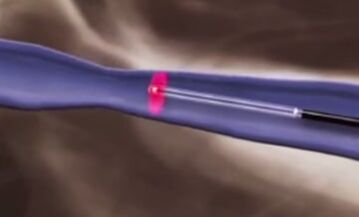

Varikoz tomirlarini davolashning termal usullari endovenoz lazer koagulyatsiyasi (EVLC) va pastki ekstremitalarning tomirlarini radiochastota obliteratsiyasi (RFO) hisoblanadi.

Endovenoz lazer koagulyatsiyasi varikoz tomirlarini samarali davolash usuli bo'lib, uning printsipi lazer energiyasining termal ta'siriga asoslangan. Ushbu davolash usuli 2001 yilda joriy etilgan va hozirgacha eng yaxshi usul hisoblanadi. Lazer koagulyatsiyasi bilan shikastlangan tomir lazer nurlari bilan isitiladi, bu venoz devorning kollagenini shikastlashning kuchli ta'sirini ta'minlaydi, tomirda yallig'lanish jarayonini va uning o'sishini keltirib chiqaradi. Ushbu usul bilan davolanadigan oyoqlarda rivojlangan varikoz tomirlari butunlay va izsiz regressiyaga uchraydi va uning asosiy belgilari yo'qoladi: shish, oyoqlarda og'irlik, terining giperpigmentatsiyasi.

EVLT teri teshilishi orqali varikoz tomirlarining lümenine lazer tolasini o'rnatish bilan boshlanadi, u zararlangan tomir bo'ylab qobiliyatsiz qopqoq joyiga yo'naltiriladi. Bemor uchun bu usul kasallikning yanada rivojlanishini va uning asoratlarini oldini olishning xavfsiz, og'riqsiz va ishonchli usuli hisoblanadi. EVLT usulini to'g'ri qo'llash bilan bemorlarning 98% da varikoz tomirlarini to'liq bartaraf etish kuzatiladi. Ushbu usulning imkoniyatlari ayollarda oyoqlardagi varikoz tomirlarini davolashga va trofik yaralarda venoz chiqishini tuzatishga imkon beradi.